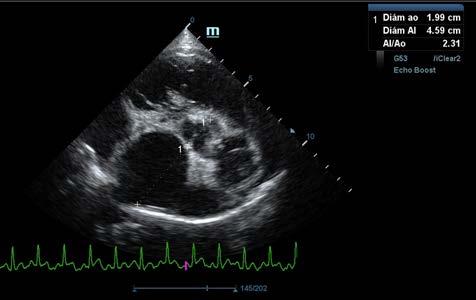

Se realiza ecocardiografía en la cual observamos engrosamiento de la válvula mitral (Fig. 2) y alteración de la estructura de las cámaras cardiacas: ratio atrio izquierdo/aorta 2,25 (Fig. 3), diámetro de ventrículo izquierdo en diástole normalizado (DVIdn) 1,98, patrón de flujo transmitral pseudonormal con velocidad máxima de onda E de 1,7 m/s, tiempo de relajación

isovolumétrica (TRIV) acortado, 30 ms, y regurgitación mitral de hasta 4,6 m/s. En la ecocardiografía se observa también una masa hiperecoica bien definida de hasta 7 x 4,3 cm de diámetro en la base aórtica (Fig. 4) y un acúmulo de derrame pericárdico leve que no permite la pericardiocentesis. Además, se detecta un nódulo hiperecoico redondeado de 1,56 cm de diámetro en la válvula tricúspide (Fig. 5).

Figura 2. Ecocardiografía en corte paraesternal izquierdo eje largo, de 4 cámaras en la que se observa engrosamiento de la válvula mitral (flecha). Figura 3. Ecocardiografía en corte paraesternal derecho eje corto en base de corazón, visualizando ratio atrio izquierdo/aorta aumentado. Figura 4. Ecocardiografía en corte paraesternal izquierdo en base de corazón, en las que se observa la estructura hiperecoica y heterogénea junto a la aorta en un corte de la lesión transversal (A) y otro longitudinal (B). Compatible con neoplasia. A B Figura 5. Ecocardiografía en corte paraesternal izquierdo eje largo, optimizada para válvula tricúspide en la que se observa estructura hiperecoica.

La ecocardiografía es el método de elección para confirmar el diagnóstico de EDVM y estimar la severidad de la regurgitación mitral. Los hallazgos ecocardiográficos incluyen el engrosamiento y/o prolapso de las hojas mitrales junto con la identificación de la regurgitación mediante Doppler. Como se comprobó en el estudio post mortem en nuestro caso, a menudo se observan alteraciones en la válvula tricúspide, pero suelen ser menos marcadas que las de la válvula mitral.2 La ecocardiografía permite adquirir dimensiones del AI en relación con la aorta, o valoración del diámetro del VI en diástole y sístole, muy útiles para estimar el grado de remodelación (agrandamiento) cardíaco.2